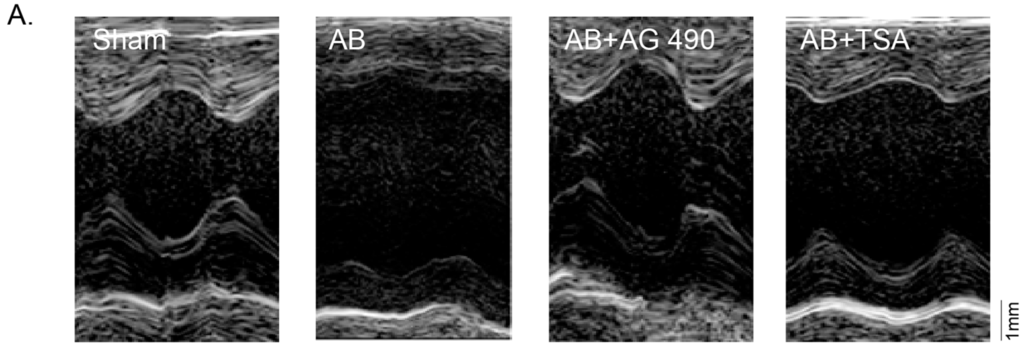

2.3. AG-490 or TSA Inhibits Pressure Overload-Induced Cardiac Hypertrophy in Vivo